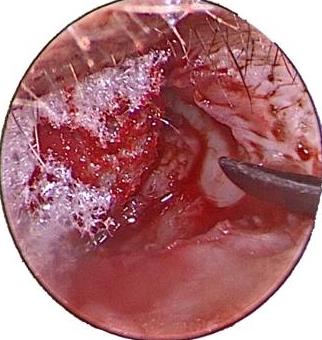

摘要:目的 探究经中鼻甲基板入路的手术技巧及临床效果,旨在系统评估一种兼具良好手术视野和微创性的蝶窦开放径路。方法 回顾性分析2019年9月-2023年9月该院收治的35例孤立性蝶窦病变或单侧蝶窦伴毗邻筛窦受累患者的临床资料,均经中鼻甲基板入路的“四步”程序化操作开放蝶窦。观察手术相关情况和并发症发生情况;采用视觉模拟评分法(VAS)评分,评估头痛和流涕等症状改善情况;采用改良隆德-肯尼迪(MLK)评分,评价术腔恢复状况。结果 所有患者术中保留钩突、中鼻甲和筛泡,26例(74.3%)保留上鼻甲;所有患者均达到临床治愈标准,表现为:术腔引流通畅,黏膜完全上皮化,以及蝶窦开口维持良好开放状态。术后病理显示:蝶窦霉菌病19例(54.3%),蝶窦息肉7例(20.0%),蝶窦黏膜慢性炎症9例(25.7%)。所有患者均未发生严重并发症,仅1例(2.9%)于术后12 d出现中鼻甲创面渗血,经电凝止血后治愈。头痛VAS评分由术前的(4.71±1.66)分,降至术后的(0.83±0.39)分,手术前后比较,差异有统计学意义(t = 13.71,P < 0.01);流涕VAS评分由术前的4.00(0.00,6.00)分,降至术后的0.00(0.00,1.00)分,手术前后比较,差异有统计学意义(Z = -4.47,P < 0.01);手术前后嗅觉减退VAS评分比较,差异无统计学意义(P > 0.05)。MLK评分由术前的4.50(2.00,4.00)分降至1.00(0.00,1.00)分,手术前后比较,差异有统计学意义(Z = -5.20,P < 0.01)。结论 经中鼻甲基板入路蝶窦开放术,严格遵循鼻窦解剖层次,在最大限度地保留鼻腔生理结构的前提下,可获得理想的术野暴露。该术式对于局限于蝶窦及后组筛窦的病变,具有确切的临床疗效。值得应用于临床。